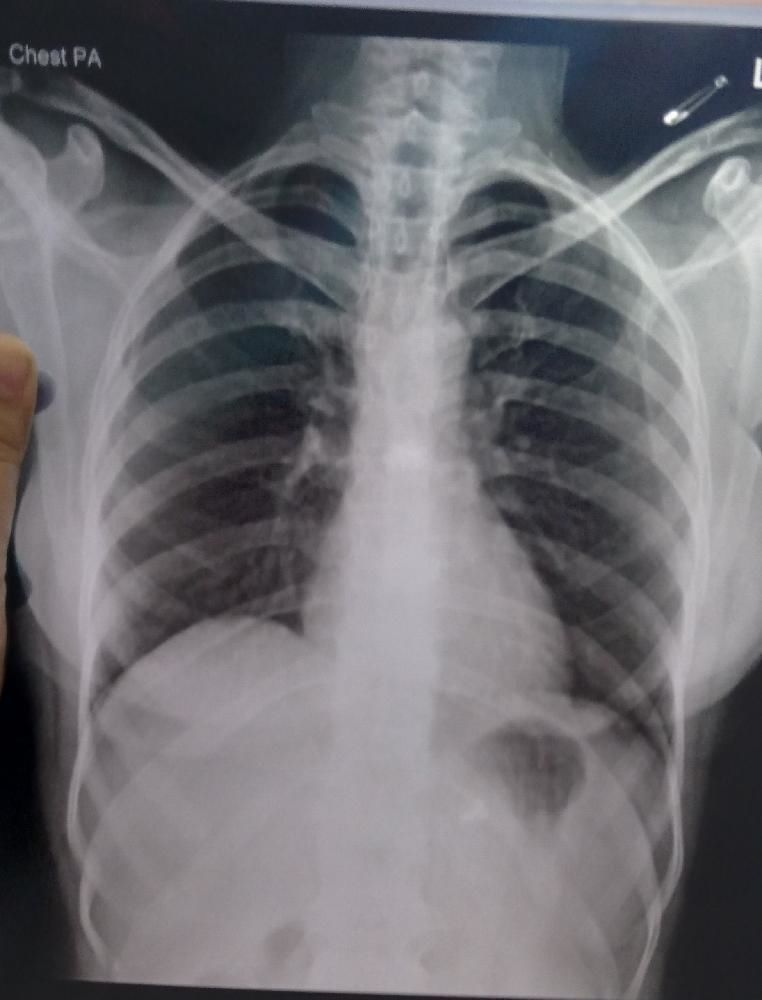

Ventricular septal defect isang butas sa dingding sa pagitan ng mga mas mababang silid ng iyong puso Paano ito nasuri. Ang butas na ito ay karaniwang naroroon sa puso bago ipanganak. Sa X-ray naman sa dibdib maaaring matukoy ang ilang impeksyon at kondisyon sa baga panlalaki ng puso pagbabara sa mga pangunahing ugat-daluyan ng dugo at mga tumor sa dibib.

X Ray Ng Dibdib Therapies 2021